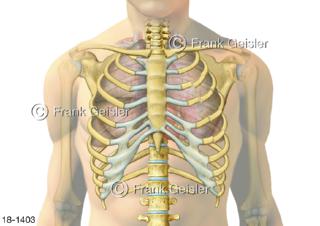

18-1403 Notfall, doppelter Rippenserienbruch Rippenserienfraktur Serienbruch der Rippen